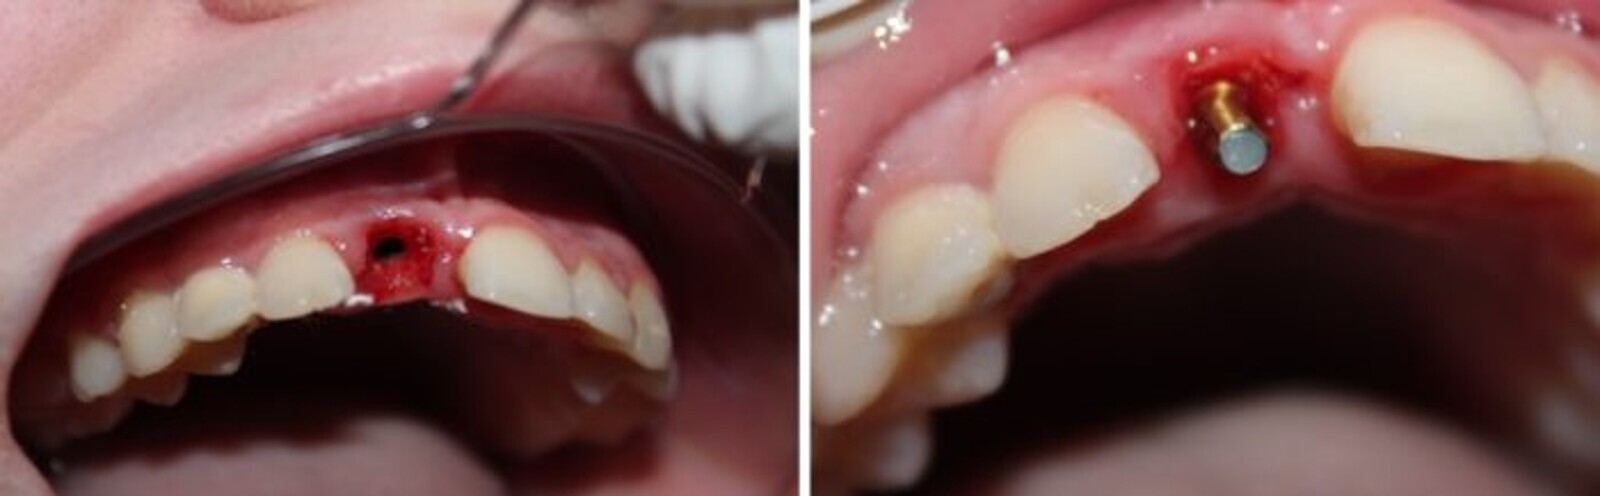

Fig. 4. Pieza 11 con desgastes proximales para la lograr exodoncia no traumática.

Fig. 5. Implante rectos NTI colocados sin realizar incisión ni sutura.

El fresado propuesto por el sistema es a 50 y 150 r.p.m. y sin irrigación para permitir la afluencia sanguínea3. El implante posee un tratamiento superficial que acelera la integración y permite activar el implante a los tres meses4. Se instala con un torque de entre 8 y 12 Newtons.

Al paciente de 16 años en el momento de la cirugía, se le confeccionó una placa termo-moldeable con alivio en la zona implantar y dientes de acrílico para resolver la estética.